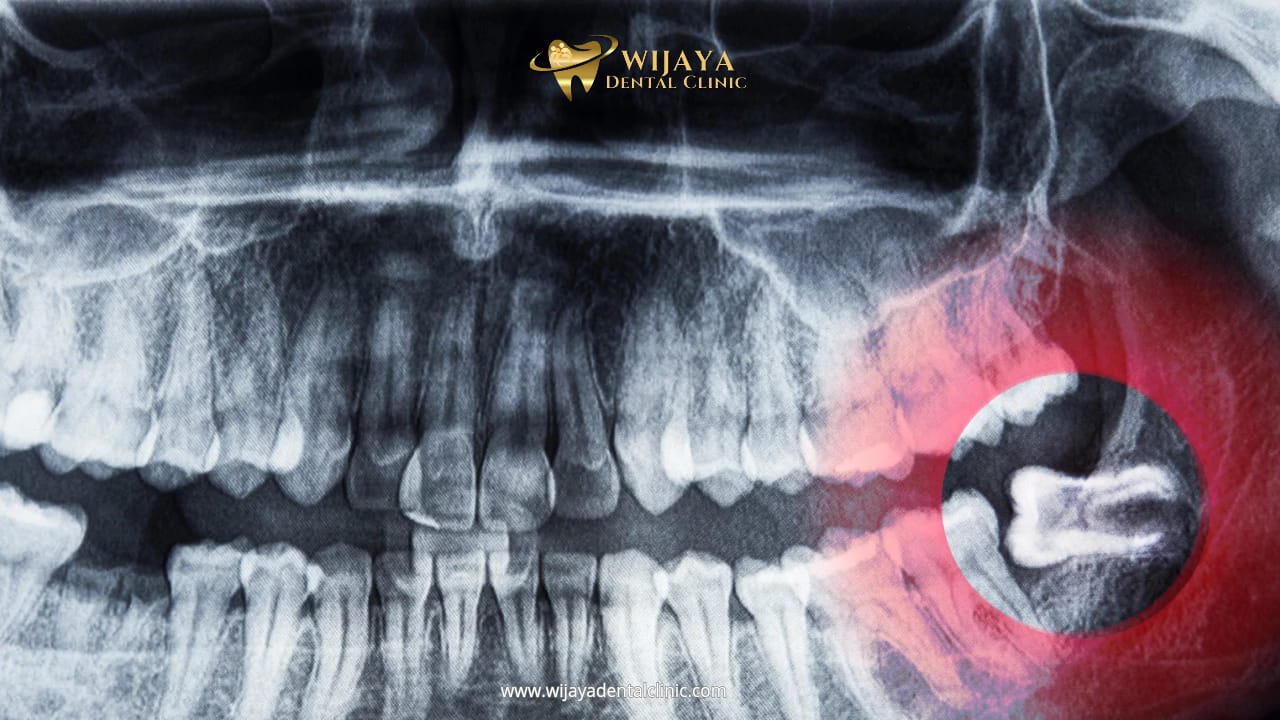

Impaksi terjadi ketika gigi bungsu tidak bisa tumbuh sempurna karena terhalang gigi di depannya, gusi, atau tulang rahang. Gigi bungsu yang impaksi biasanya tumbuh miring, terjepit, atau bahkan sepenuhnya tertanam di bawah gusi. Kondisi ini dapat menyebabkan nyeri hebat, terutama saat mengunyah atau membuka mulut lebar.

Selain itu, impaksi berisiko menimbulkan tekanan pada gigi di sebelahnya, sehingga bisa menyebabkan pergeseran posisi gigi dan membuat gigi lain menjadi tidak rata. Jika dibiarkan, impaksi juga dapat memicu infeksi yang menyebar ke jaringan lain di sekitar mulut.